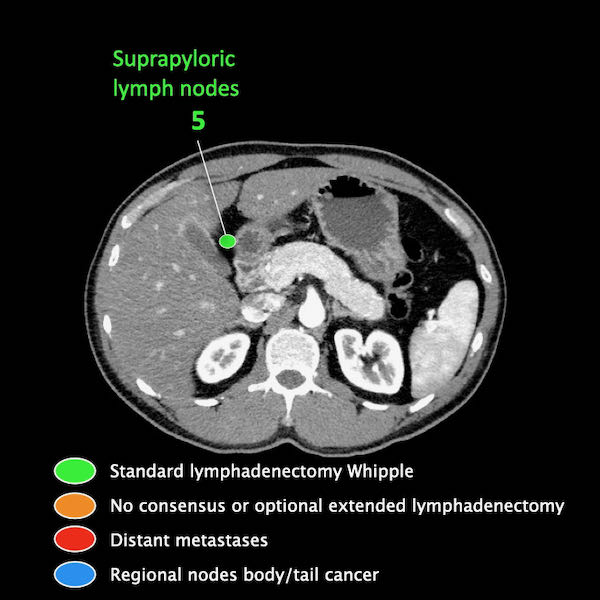

Điều quan trọng là phân biệt giữa hạch bạch huyết vùng và hạch bạch huyết ngoài vùng (di căn xa).

Các vị trí ngoài vùng chính là cạnh động mạch chủ và bên trái SMA.

Các hạch nghi ngờ ở những vị trí này cần được ghi nhận và sinh thiết.

Trong hình minh họa này, chúng tôi sử dụng các trạm hạch bạch huyết trong ung thư tụy theo đề xuất của Hội Tụy học Nhật Bản.

Danh sách đầy đủ được cung cấp trong chương về báo cáo. Nhấn vào đây.

Di căn hạch bạch huyết là yếu tố tiên lượng quan trọng và xảy ra ở khoảng hai phần ba bệnh nhân ung thư tụy có khả năng cắt bỏ.

Các chặng hạch bạch huyết trong ung thư tụy

Các chặng hạch bạch huyết trong ung thư tụy theo đề xuất của Hội Tụy học Nhật Bản.